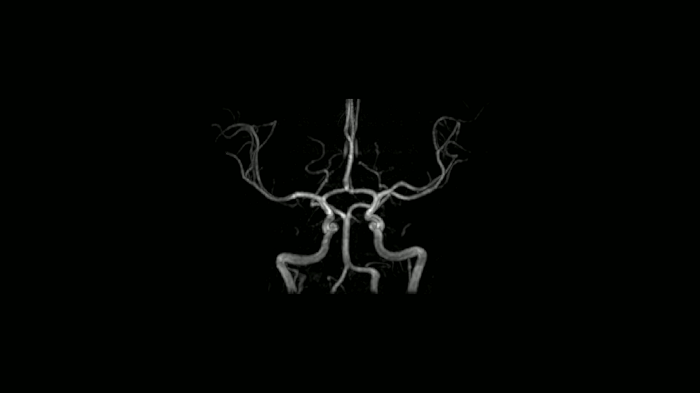

Time-of-flight angiography

Non-contrast enhanced angiography of the cranial vessels is used to detect vessel occlusions or aneurysms. High-resolution ToF angiography can also show small arteries for subtle diagnoses.

Image Courtesy: University Hospital Erlangen, Germany | Image-ID: 4aaaa0466